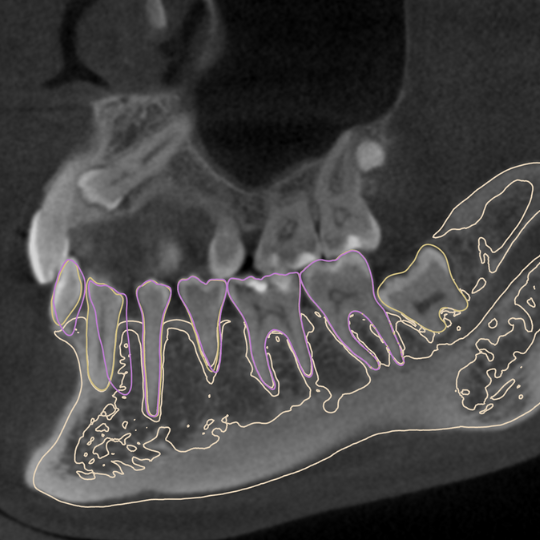

KISS Aligner este un sistem de aliniere dentară transparent, similar cu alte produse populare precum Invisalign. Acesta folosește o serie de gutiere transparente pentru a corecta poziția dinților și pentru a îmbunătăți alinierea acestora.

Evaluând atent fiecare caz și aplicând cele mai recente cunoștințe și tehnici pentru a înțelege și de a gestiona corect tulburările articulației temporomandibulare, putem îmbunătăți calitatea vieții pacienților noștri și putem oferi un suport medical adecvat pentru această afecțiune complexă.